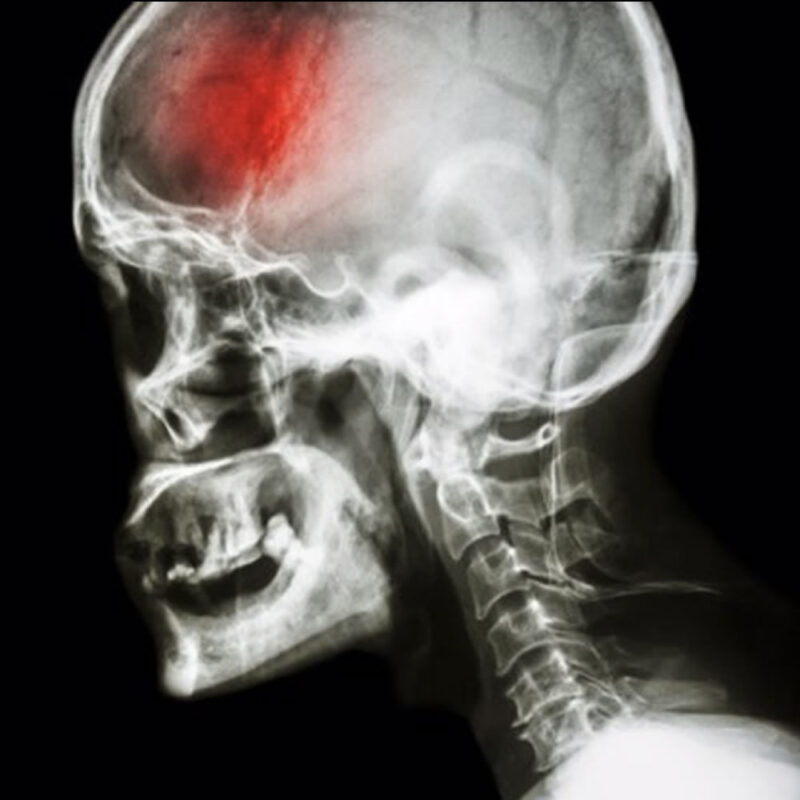

Traumatismo encéfalo-craneal

Nuestro equipo tiene una alta experiencia en el manejo y tratamiento del traumatismo encéfalo-craneal en pediatría, permitiéndonos lograr un óptimo resultado funcional. Trabajamos con otros especialistas en equipo multidisciplinario de primer nivel, y en Centros de...